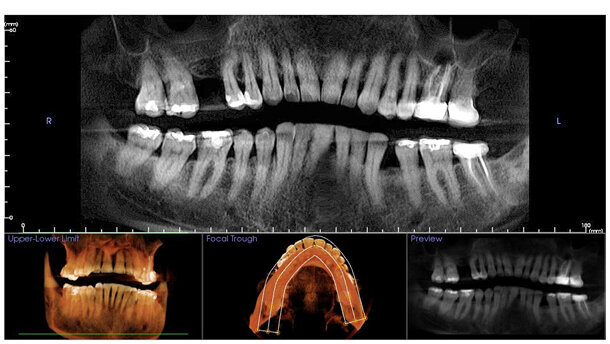

El autor asegura en este artículo que las imágenes tridimensionales que proporciona la tomografía computarizada de haz cónico (CBCT) revelan detalles anatómicos únicos de cada paciente que son imposibles de detectar por otros medios, razón por la que se ha convertido en una herramienta fundamental para la colocación de implantes dentales.

El advenimiento de la tomografía computarizada a finales de la década de 1980 expandió considerablemente la capacidad clínica para visualizar la anatomía de nuestros pacientes, limitada hasta entonces a la radiografía convencional periapical bidimensional o la radiografía panorámica. En principio se utilizó como una herramienta para ayudar a entender el complejo maxilomandibular para la colocación de implantes dentales. Sin embargo, su costo, poca disponibilidad y alta radiación limitaron el uso de esta tecnología. Además, las escuelas dentales no ofrecían cursos de tomografía computarizada. La mayoría de estas barreras desaparecieron con la llegada de la tomografía computarizada de haz cónico (CBCT, por sus siglas en inglés) a principios de la década del 2000. Poco a poco, los tomógrafos CBCT entraron en el mercado y en los consultorios, ofreciendo a los odontólogos un acceso inmediato a esta tecnología de visualización. La evolución de la tecnología trajo consigo sensores más sofisticados, mejoras como campo visual grande y pequeño (FOV) y programas que combinan datos con innovadores programas digitales interactivos para la planificación de tratamientos dentales, lo cual ha ampliado el alcance y la capacidad de esta herramienta diagnóstica (Figura 1).